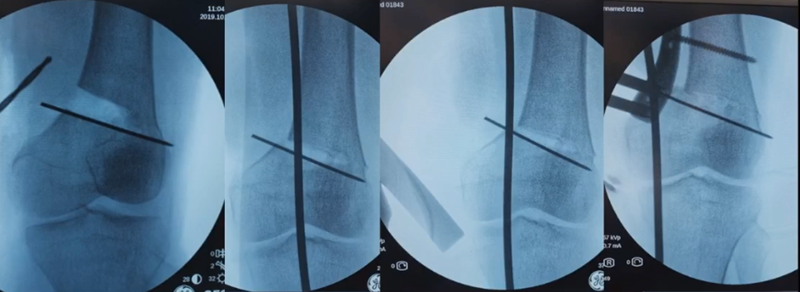

合页点和截骨线已确定好,按照术前计划打入导针,测量截骨深度。

注意,目前临床推荐的DFO要求最好能做双平面截骨,即还要有一条上行截骨线,上行截骨线与水平截骨线夹角大概为95° 左右。这种截骨方式一方面可以增加稳定性,同时也可以减少对上方髌股关节的干扰。

上行截骨时,要保持肢体旋转中立位,前方要有骨撬保护,由内向外完全截开,上行截骨线不存在合页。

水平截骨时,同样放肢体中立位,后侧放一把骨撬保护后方重要结构。

截骨过程中,不要求一次截骨到位,把合页深度全部截到,可以留最后一点,用钻头由前向后打出一排筛孔来,把合页端弱化,再去做闭合时就不容易折断了。